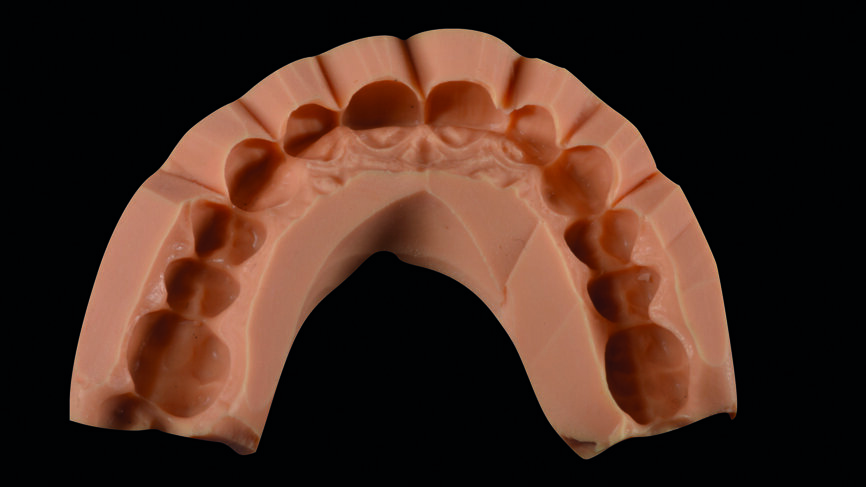

Fig. 4 : Warm-up sur le modèle en plâtre pierre en vue du traitement de restauration des dix dents antérieures.

Les principes de Coachman et Calamita9 ont été suivis pour concevoir numériquement le sourire et ont donné lieu à un plan de traitement d‘élongation coronaire et de pose des facettes sur les dents 15 à 25 (Fig. 3). Une maquette classique en cire diagnostique a également été réalisée (Fig. 4) ainsi que des mock-ups traditionnels et numériques puis les formes dentaires et leurs proportions ont été approuvées pat la patiente.

Le jeu de facettes en céramique feldspathique a été fabriqué en IPS Style (Ivoclar Vivadent) sur un modèle en plâtre-pierre, tandis qu‘un bloc IPS Empress CAD Multi (Ivoclar Vivadent) a été utilisé pour le jeu numérique (Figs. 13 et 14). Les deux jeux ont été évalués en bouche avec une pâte d‘essai afin de comparer les propriétés optiques des facettes feldspathiques et des facettes réalisées en technique CFAO (Figs. 15a–c).